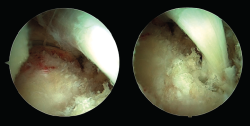

Una vez el tendón está dentro del túnel, debe ser bloqueado con un tornillo interferencial o de biotenodesis. Idealmente, el tornillo debe ser del mismo diámetro que el túnel calcáneo realizado. El tornillo se introduce guiado con un nitinol para que tome una dirección correcta. Con el tobillo en flexión plantar y traccionando de las suturas para tensar el tendón FHL, se introduce el tornillo bajo control endoscópico directo (Figura 7).

Figura 7. Visión final de la transferencia del tendón flexor hallucis longus (FHL). Izquierda: visión proximal; derecha: visión distal con visualización del tendón del FHL correctamente fijado al calcáneo con un tornillo interferencial.